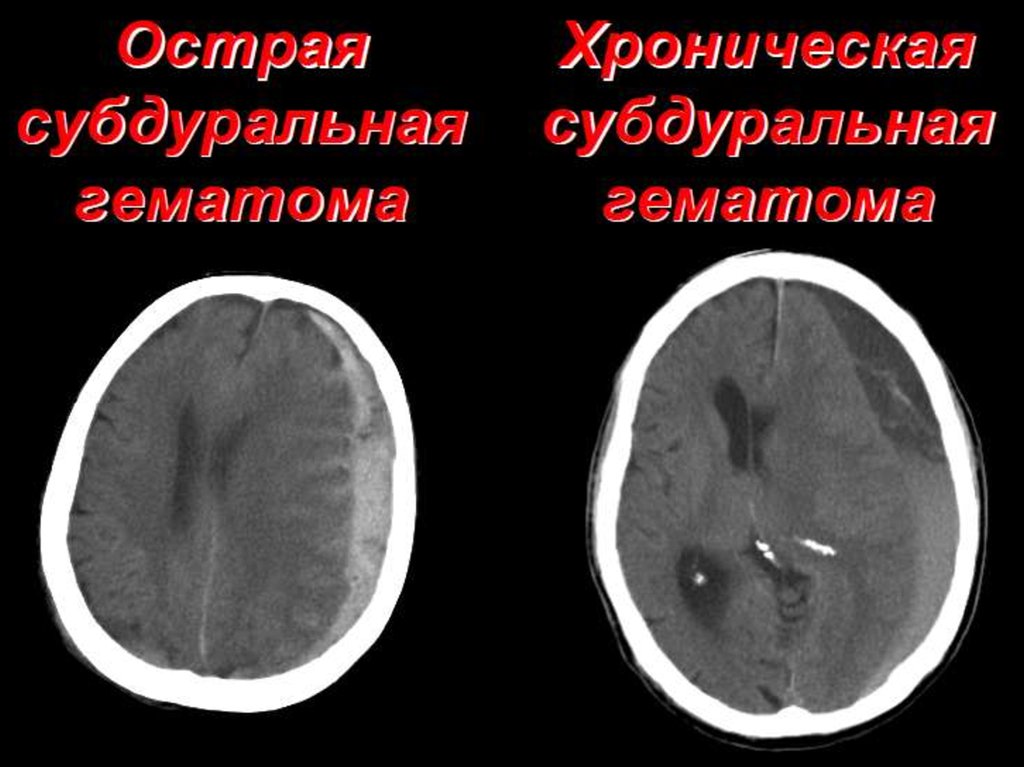

ЧЕРЕПНО-МОЗГОВАЯ ТРАВМА, ПОЗВОНОЧНОСПИННОМОЗГОВАЯ ТРАВМА